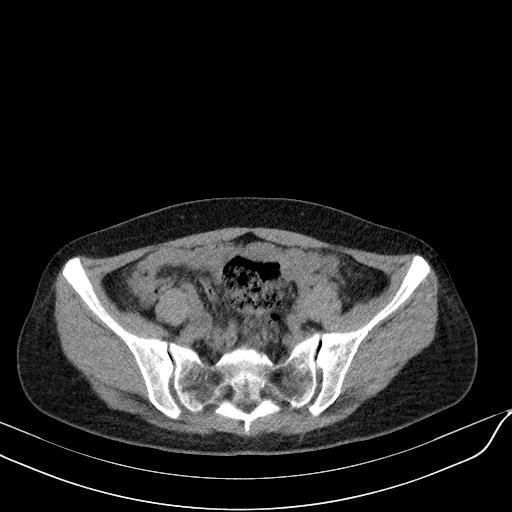

标题: CT23965:无外伤史,下腹痛 [打印本页]

标题: CT23965:无外伤史,下腹痛

肠道未准备,继续往下扫,乙状结肠占位不排除。建议钡灌或结肠镜检查。

乙状结肠占位不排除

未见明显异常改变,做个气钡双重造影除外一下结肠病变,无外伤史为啥不常规喝泛影葡胺水对比剂再扫ct呢?

回肠间质瘤?

肠道肿瘤,建议行钡剂灌肠检查。